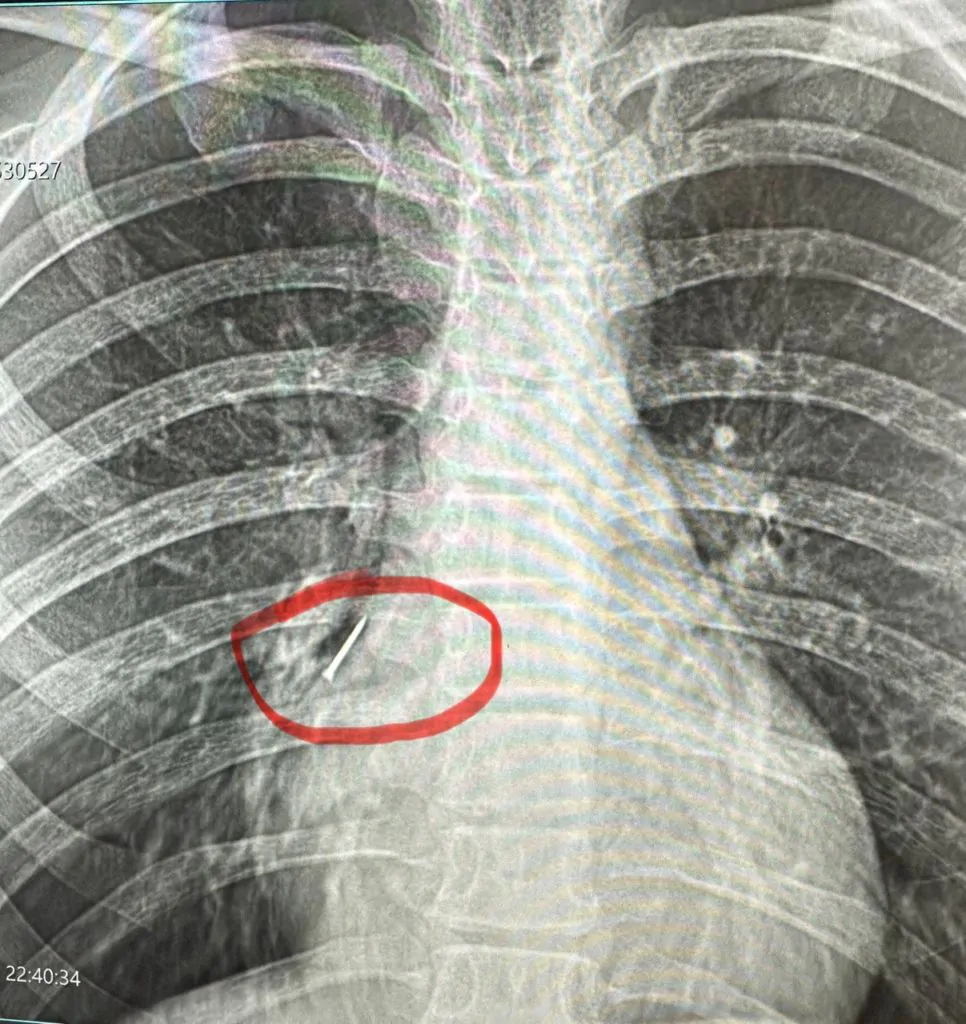

«Водночас, — розповідає хірург дитячий Василь Демчук, — клінічна картина не була типовою для апендициту.

Після додаткових обстежень, зокрема рентгенографії, з’ясувалося, що у кишківнику дитини сторонні тіла».

Під час операції лікарі виявили магніти, два з яких склеїлись між собою у різних відділах кишківника. В місці з’єднання утворився пролежень, а згодом — перфорація, внаслідок чого кишковий вміст витік у черевну порожнину.

«Непросто було видалити й магніти. Їх довелося «завести» в апендикс і видалити разом із ним. Дівчинку виписали додому на 10-й день після оперативного втручання», — Василь Демчук.